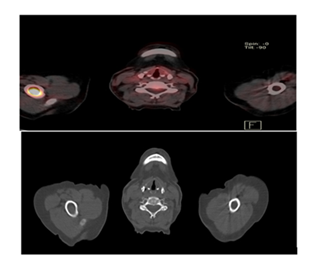

A 70-year-old male patient visited the outpatient clinic with a past medical record of diabetes type II, arterial hypertension under treatment and a history of three months with fatigue, nonproductive cough and dyspnea. During the clinical examination the patient was found to be afebrile and presented on auscultation with respiratory wheezing and presence of abundant crackles in the left hemithorax. The patient’s blood test showed mild anemia with a hemoglobin level 10.9g/dl, the white blood cell count was slightly elevated at 11.8 × 10³/µL due to an increase on neutrophils. Tumor markers showed a CEA (carcinoembryonic antigen) level of 88 U/mL, which is higher than normal. Additional imaging was performed with a chest computed tomography, which revealed a right upper lung solid mass measuring 51x44mm, accompanied with carcinomatous lymphangitis. The patent underwent an 18F-FDG PET/CT scan to assess the extent of the disease. In addition to the pulmonary lesion and carcinomatous lymphangitis, bone lesions were also identified. There were two lesions, one in the right humeral diaphysis, with high radiotracer uptake, (SUV max 8.8), and another in the left iliac bone with similar characteristics (SUV max 14.2). These lesions are PET positive, but not visible on computed tomography, suggesting early bone metastases.